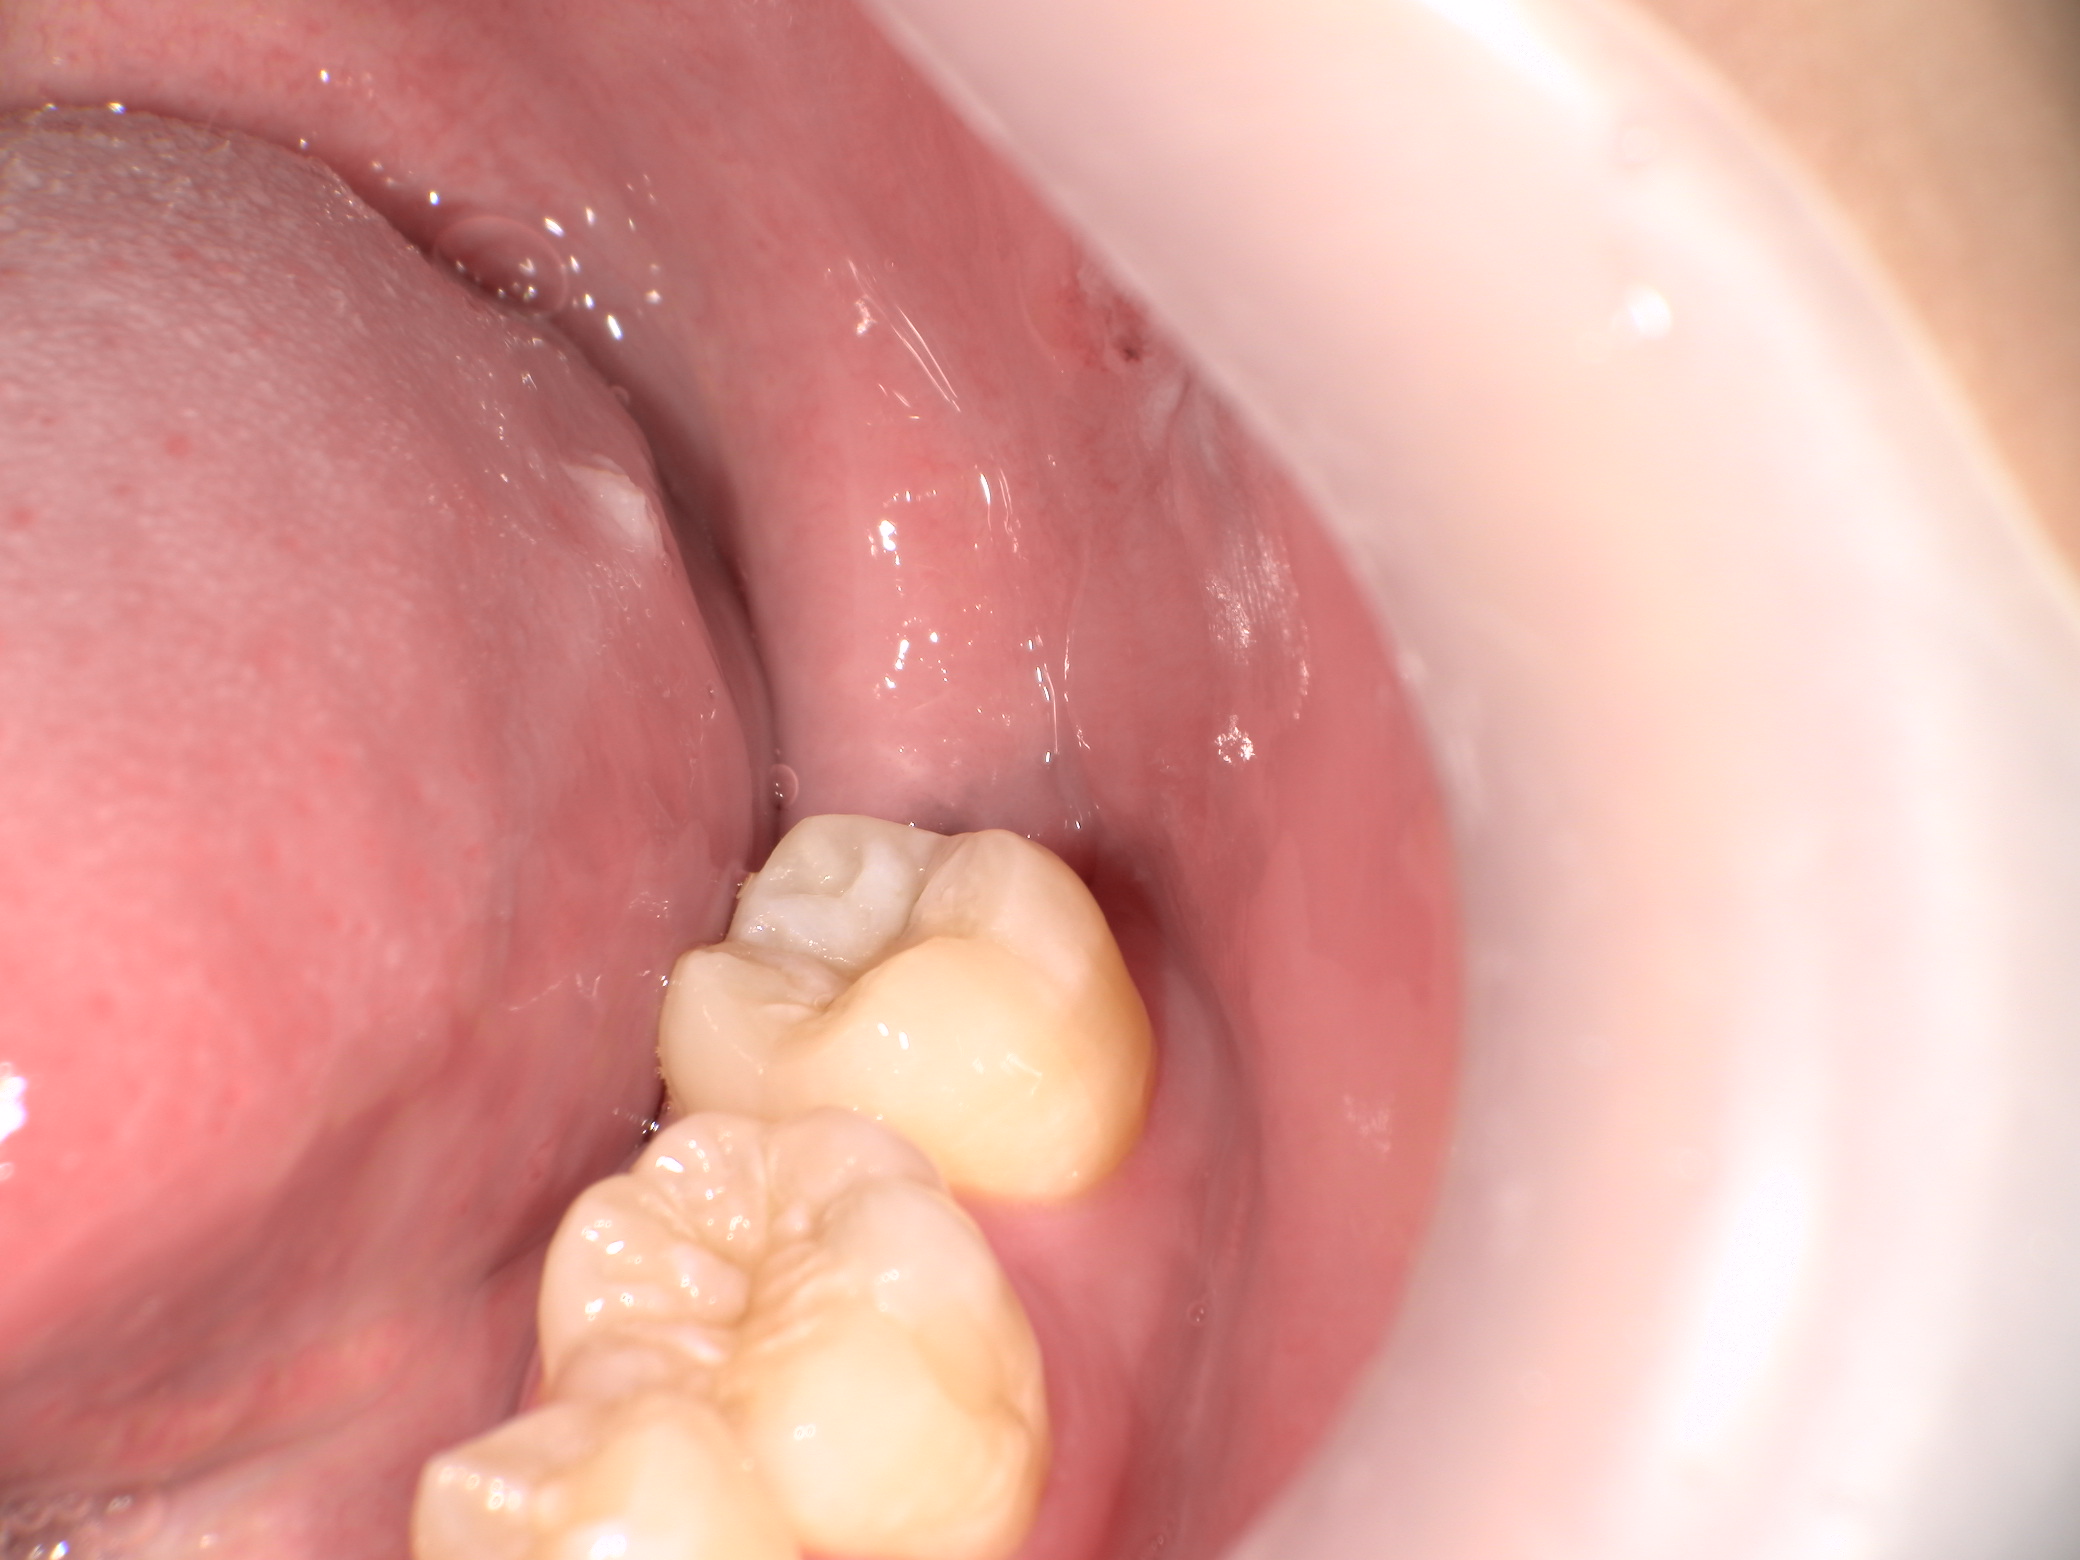

親知らずは歯茎と骨の中に埋まっています。

将来、智歯周囲炎や手前の歯に悪影響が及ばないように抜歯することとなりました。

事前にCTを撮影し位置や方向だけでなく、歯冠・歯根形態も把握済みです。

切開して歯冠部周囲の骨を削ります。

頭を囲む骨はなくなり、親知らずの歯冠部が見えてきましたがまだ抜けません。歯は基本的に頭側の方向にしか抜けません。

斜めに向いているのでこのままでは手前の歯にぶつかってしまいます。